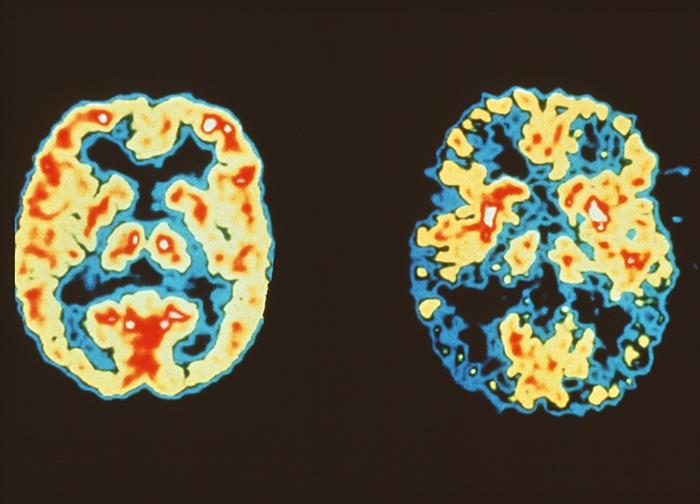

2. تشخیص زوال عقل: آزمایشهای تصویربرداری

پزشک شما ممکن است آزمایشهای تصویربرداری زیر را برای بررسی مغز شما تجویز کند:

- اسکن FDG-PET: این نوع ویژهای از اسکن مغز است که برای تعیین عملکرد مغز و کاهش شناختی با الگوی جذب نوعی گلوکز توسط بافت مغز کمک میکند و در برخی تشخیصها مورد نیاز است.